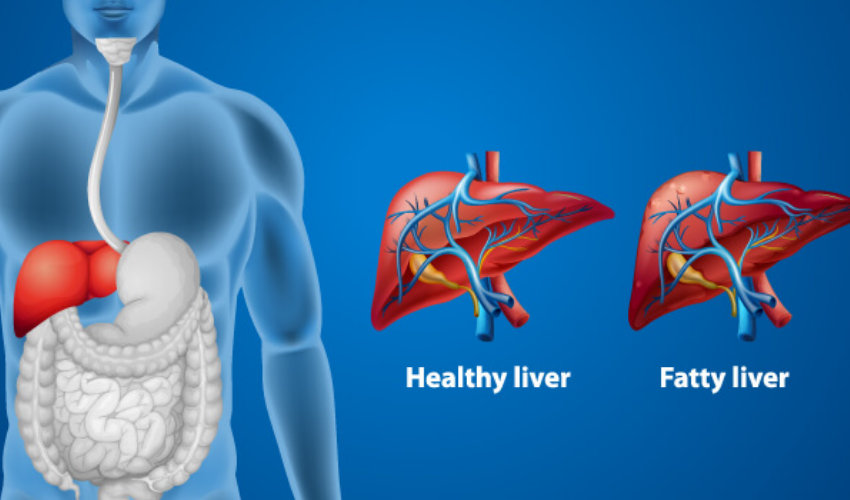

Early detection is key. Fatty liver and hepatitis are fully reversible in their initial stages. But delay can lead to fibrosis or cirrhosis, which is difficult to reverse. One of the most common liver issues seen today is fatty liver disease. It can happen even to those who don’t drink alcohol. The main causes are poor diet, obesity, and sedentary habits. In the early stages, fatty liver is reversible — but if left untreated, it can progress to liver fibrosis or cirrhosis. That’s why Dr. Sathish Gadigoppula recommends every adult above 30 get a liver screening once a year.